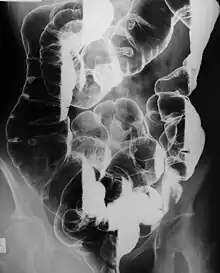

Peutz–Jeghers syndrome (often abbreviated PJS) is an autosomal dominant genetic disorder characterized by the development of benign hamartomatous polyps in the gastrointestinal tract and hyperpigmented macules on the lips and oral mucosa (melanosis).[1] This syndrome can be classed as one of various hereditary intestinal polyposis syndromes[2] and one of various hamartomatous polyposis syndromes.[3] It has an incidence of approximately 1 in 25,000 to 300,000 births.[4]

The risks associated with this syndrome include a strong tendency of developing cancer in a number of parts of the body.[5] While the hamartomatous polyps themselves only have a small malignant potential (< 3% per OHCM), patients with the syndrome have an increased risk of developing carcinomas of the liver, lungs, breast, ovaries, uterus, testes and other organs. Specifically, it is associated with an increased risk of sex-cord stromal tumor with annular tubules in the ovaries.[6]

- Hamartomatous polyps in the gastrointestinal tract. These are benign polyps with an extraordinarily low potential for malignancy.